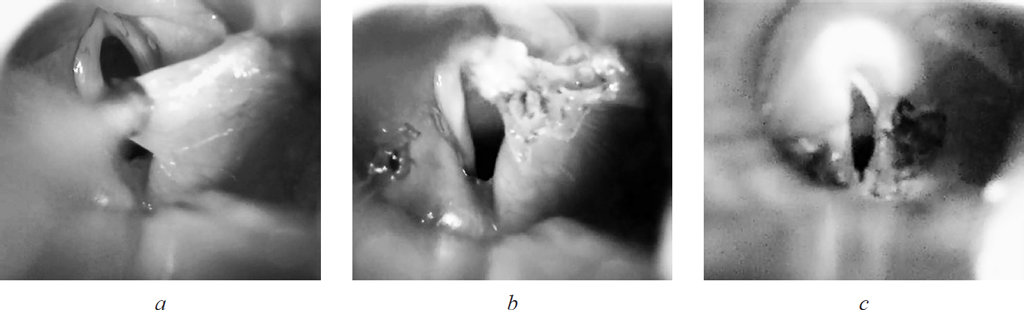

Сразу после операции отмечались купирование стридора, втяжения уступчивых мест грудной клетки. Девочка была выписана на 11-е сутки после оперативного лечения (рис. 4).

Рис. 4. Эндофотография гортани на 10-е сутки после супраглоттопластики. Сохраняется налет фибрина в области правой черпалонадгортанной складки

При контрольном осмотре через 1 месяц отмечались улучшение самочувствия, нормализация прибавки массы тела, эпизоды стридора сохранялись только на фоне эмоциональной нагрузки. Период наблюдения составил 1 год 6 месяцев.